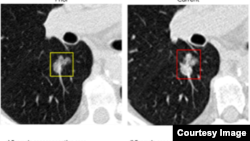

Quiz - Researchers Say AI System Greatly Improves Lung Cancer Predictions